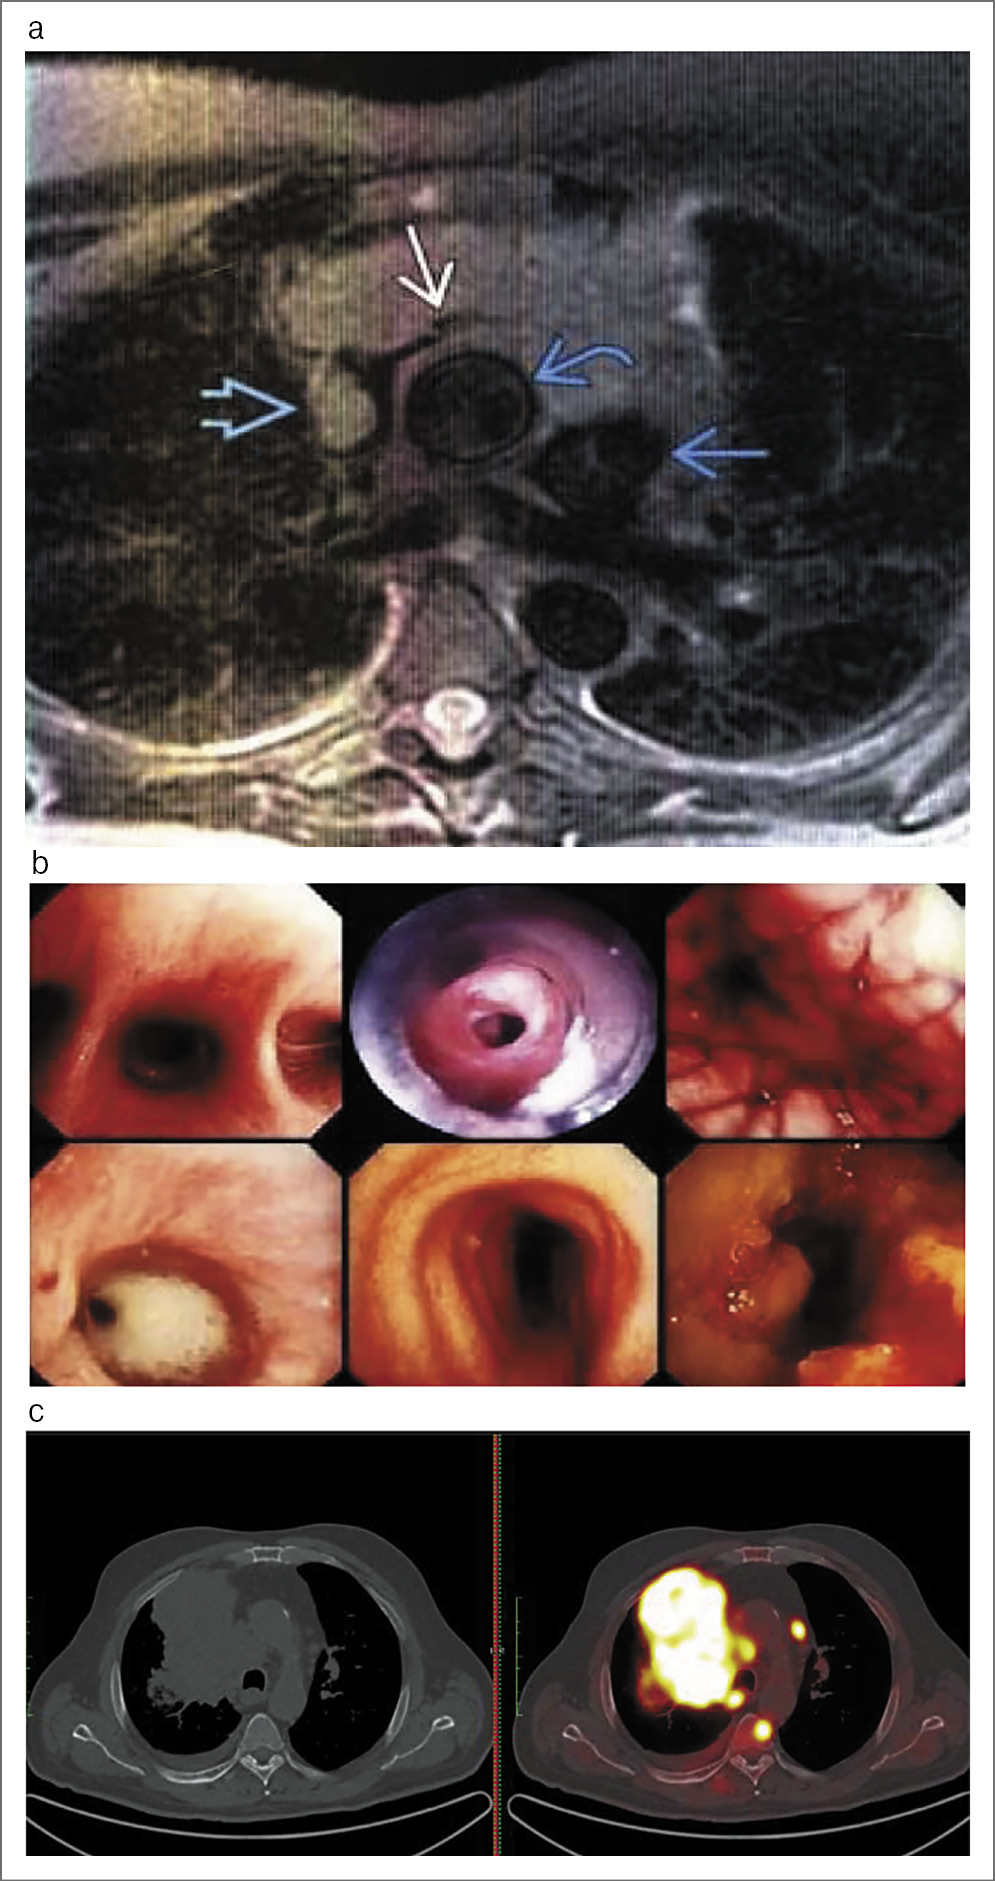

В комплекс диагностики внутригрудных гигантских образований входили и другие методы, такие как магнитно- резонансная томография (МРТ), трахеобронхоскопия, а в некоторых случаях и позитронно-эмиссионная томография (ПЭТ), совмещенная с КТ (рис. 2, a–c).

Рис. 2. Комплекс методов диагностики: а – МРТ; b – эндоскопия; c – ПЭТ/КТ.

МРТ может быть альтернативным методом МСКТ в случае непереносимости контрастного препарата с содержанием йода. Метод весьма эффективен в выявлении и оценке внутригрудного новообразования, медиастинальной лимфаденопатии, оценке магистральных сосудов и перикарда. Эндоскопическое исследование может быть более информативно в выявлении прорастания стенки трахеи и бронхов, оценке трахеобронхиальной обструкции, конечно же, возможности взятия тканей для цито- и гистологической верификации. ПЭТ/КТ не является методом ранней диагностики и применяется для оценки распространенности опухолевого процесса, выявления отдаленных и местных метастазов, так как позволяет определить зоны патологического метаболизма. Наиболее рациональным и эффективным применением ПЭТ/КТ являются оценка эффективности лечения опухолевого процесса (полихимиотерапия, лучевая терапия) и диагностика рецидивов.